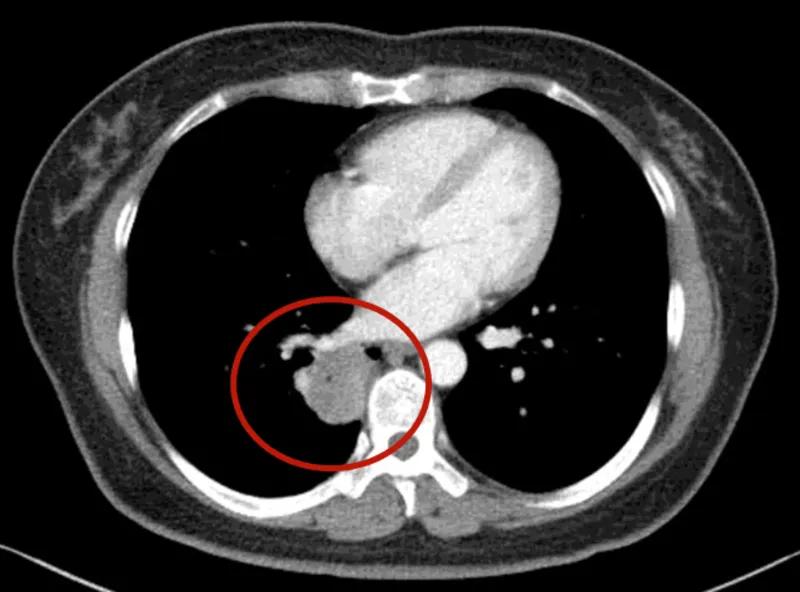

可见是右下肺达近5厘米的肿块,并上叶磨玻璃结节以及斜裂、水平裂多发微小结节。影像是如何的呢?

到底该如何考虑?下一步该如何决策?我的意见是:右下叶红色圈起来的考虑是肺癌,浸润性腺癌可能性大;右上叶磨玻璃结节粉色圈起来的考虑原位癌或不典型增生可能性大;绿色圈起来的基本上是叶裂处,从密度来看更像良性,但因为有右下叶的病灶在,也可能是种植转移,但术前较难确定。PET-CT可以考虑,但也有假阴性或假阳性。个人意见是如果没有远处其他确切转移,建议胸腔镜下探查,如果微小实性结节非转移性,则右下肺癌仍能手术的。如果真若是转移,也可取行病理依据,并送基因检测与免疫组化等检查,而单孔胸腔镜下探查下创伤小,恢复快,当然若不是转移,顺便镜下行右下叶切除并清扫淋巴结就行。